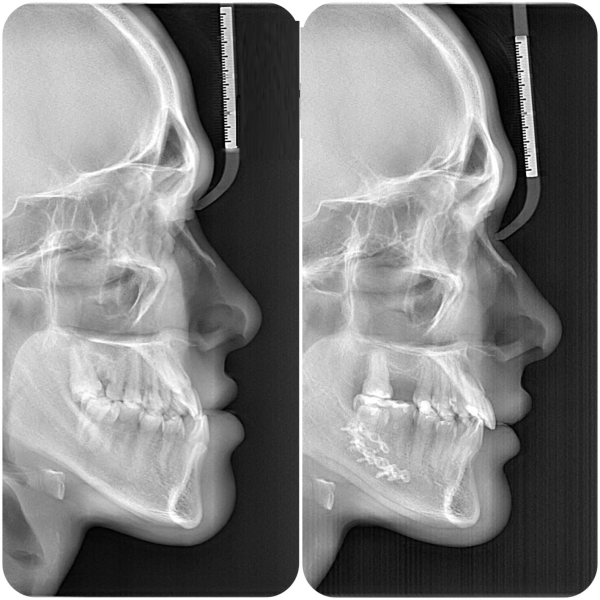

- Chụp X-quang toàn cảnh và phim Cone Beam CT để đánh giá chi tiết cấu trúc xương hàm, vị trí răng, mức độ lệch khớp cắn và sự liên quan với dây thần kinh.

- Scan răng 3D bằng máy quét trong miệng nhằm ghi lại chính xác hình dạng từng răng và cung hàm.

- Quét gương mặt 3D (FaceScan) để phân tích tổng thể tỉ lệ gương mặt, đường nét thẩm mỹ và sự cân đối giữa xương – răng – mô mềm.

Toàn bộ dữ liệu này được đồng bộ vào phần mềm mô phỏng, giúp bác sĩ lập kế hoạch phẫu thuật cá nhân hóa, dự đoán trước kết quả và đảm bảo độ chính xác tối đa.